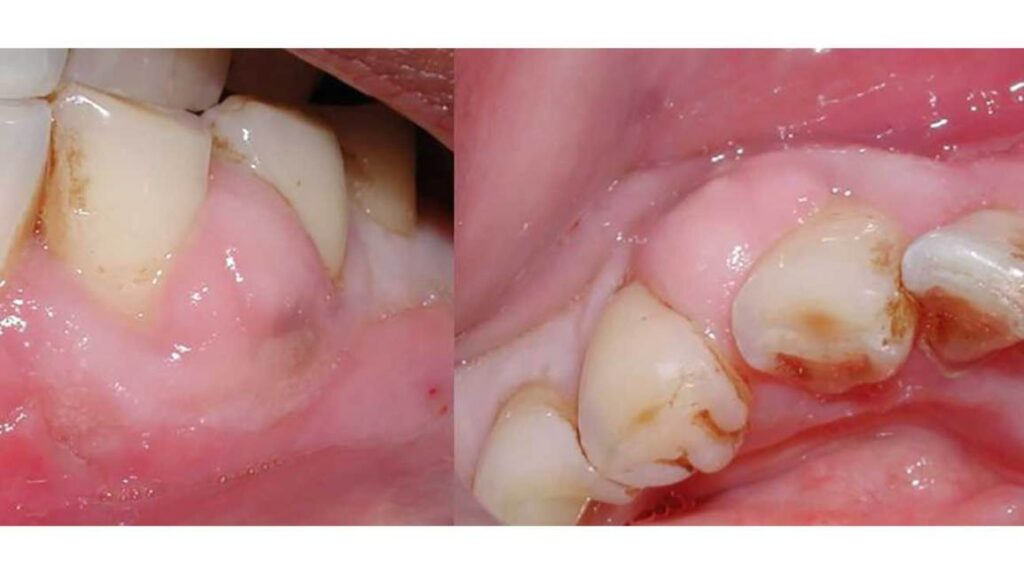

There are two main types of dental abscesses: periapical abscess and periodontal abscess. A periapical abscess occurs at the tip of the tooth’s root, while a periodontal abscess occurs in the gums next to the tooth. Both types can lead to similar complications if not properly treated.

In some cases, a dental abscess can lead to soft tissue infections in the surrounding areas. This can cause pain, swelling, and discomfort. Prompt treatment is necessary to prevent the infection from spreading further. -

If a dental abscess is not treated promptly, it can lead to tooth loss. The infection can cause extensive damage to the tooth and the surrounding structures, making it necessary to extract the affected tooth. -